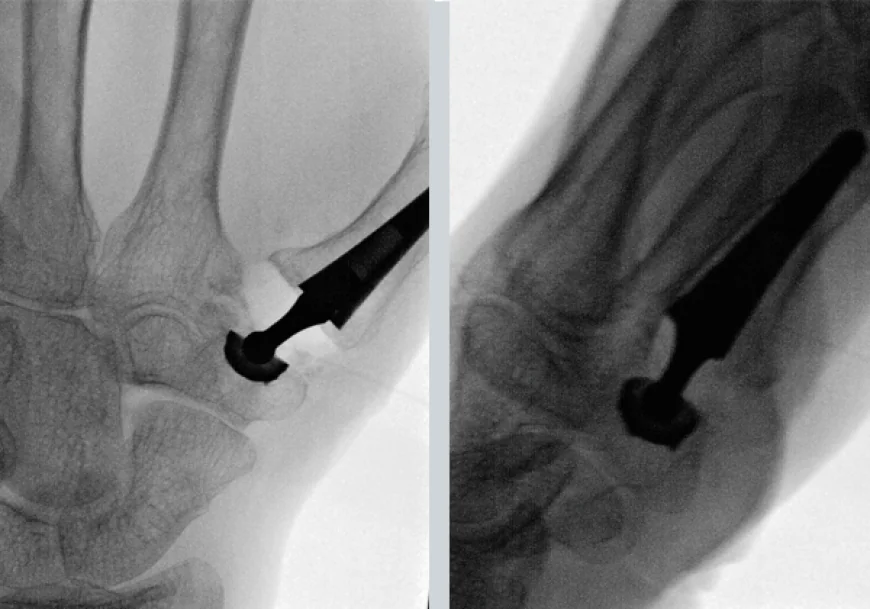

CMC joint replacement surgery, also called thumb basal joint arthroplasty, involves removing the damaged joint surfaces and replacing them with either a soft tissue spacer or an artificial implant. The goal is to relieve pain, restore thumb function, and improve hand strength.

- A tendon graft or synthetic implant is inserted as a spacer